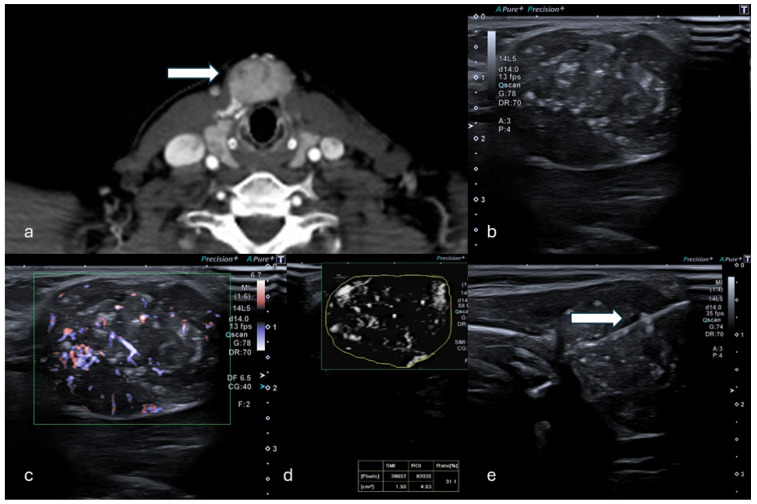

Objectives: This study aims to assess the potential role of the ultrasound (US) monochromatic Superb Microvascular Index (mSMI) to predict malignancy of solid focal lesions, correlating the vascular index (VI) with bioptic histological results.

Methods: In this single-center retrospective analysis, patients undergoing percutaneous US-guided biopsy of solid lesions were considered. Biopsy indication was given by a multidisciplinary team evaluation based on clinical radiological data. Exclusion criteria were: unfeasible SMI evaluations due to poor respiratory compliance, locations not appreciable with the SMI, previous antiangiogenetic chemo/immunotherapies, and inconclusive histological reports. The mSMI examination was conducted in order to visualize extremely low-velocity flows with a high resolution and high frame rate; the VI was semi-automatically calculated. All bioptic procedures were performed under sole US guidance using 16G or 18G needles, immediately after mSMI assessment.

Results: Forty-four patients were included (mean age: 64 years; 27 males, 17 females). Liver (15/43), kidneys (9/43), and lymph nodes (6/43) were the most frequent targets. At histopathological analysis, 7 lesions were benign and 37 malignant, metastasis being the most represented. The VI calculated in malignant lesions was statistically higher compared to benign lesions (35.45% and 11% in malignant and benign, respectively; p-value 0.013). A threshold VI value of 15.4% was identified to differentiate malignant lesions. The overall diagnostic accuracy of the VI with the mSMI was 0.878, demonstrating a high level of diagnostic accuracy.

Conclusions: In this study, the mSMI analysis of solid focal lesions undergoing percutaneous biopsy significantly correlated with histological findings in terms of malignant/benign predictive value, reflecting histological vascular changes in malignant lesions.